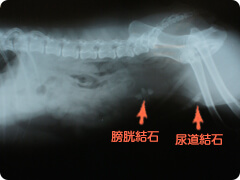

膀胱結石・尿道結石

膀胱内にできた結石は膀胱を刺激したり粘膜を傷つけ、頻尿や血尿の原因になります。

尿道内に存在する結石はカテーテルで膀胱内に戻してから膀胱切開により摘出します。